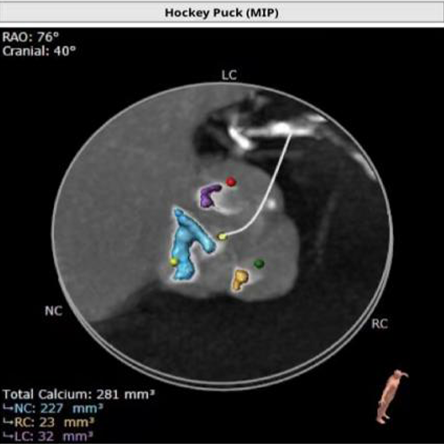

钙化积分:281mm³

工作体位:RAO:4° CAU:16° RAO:16° CAU:28° 左冠:LAO:21° CRA:9°